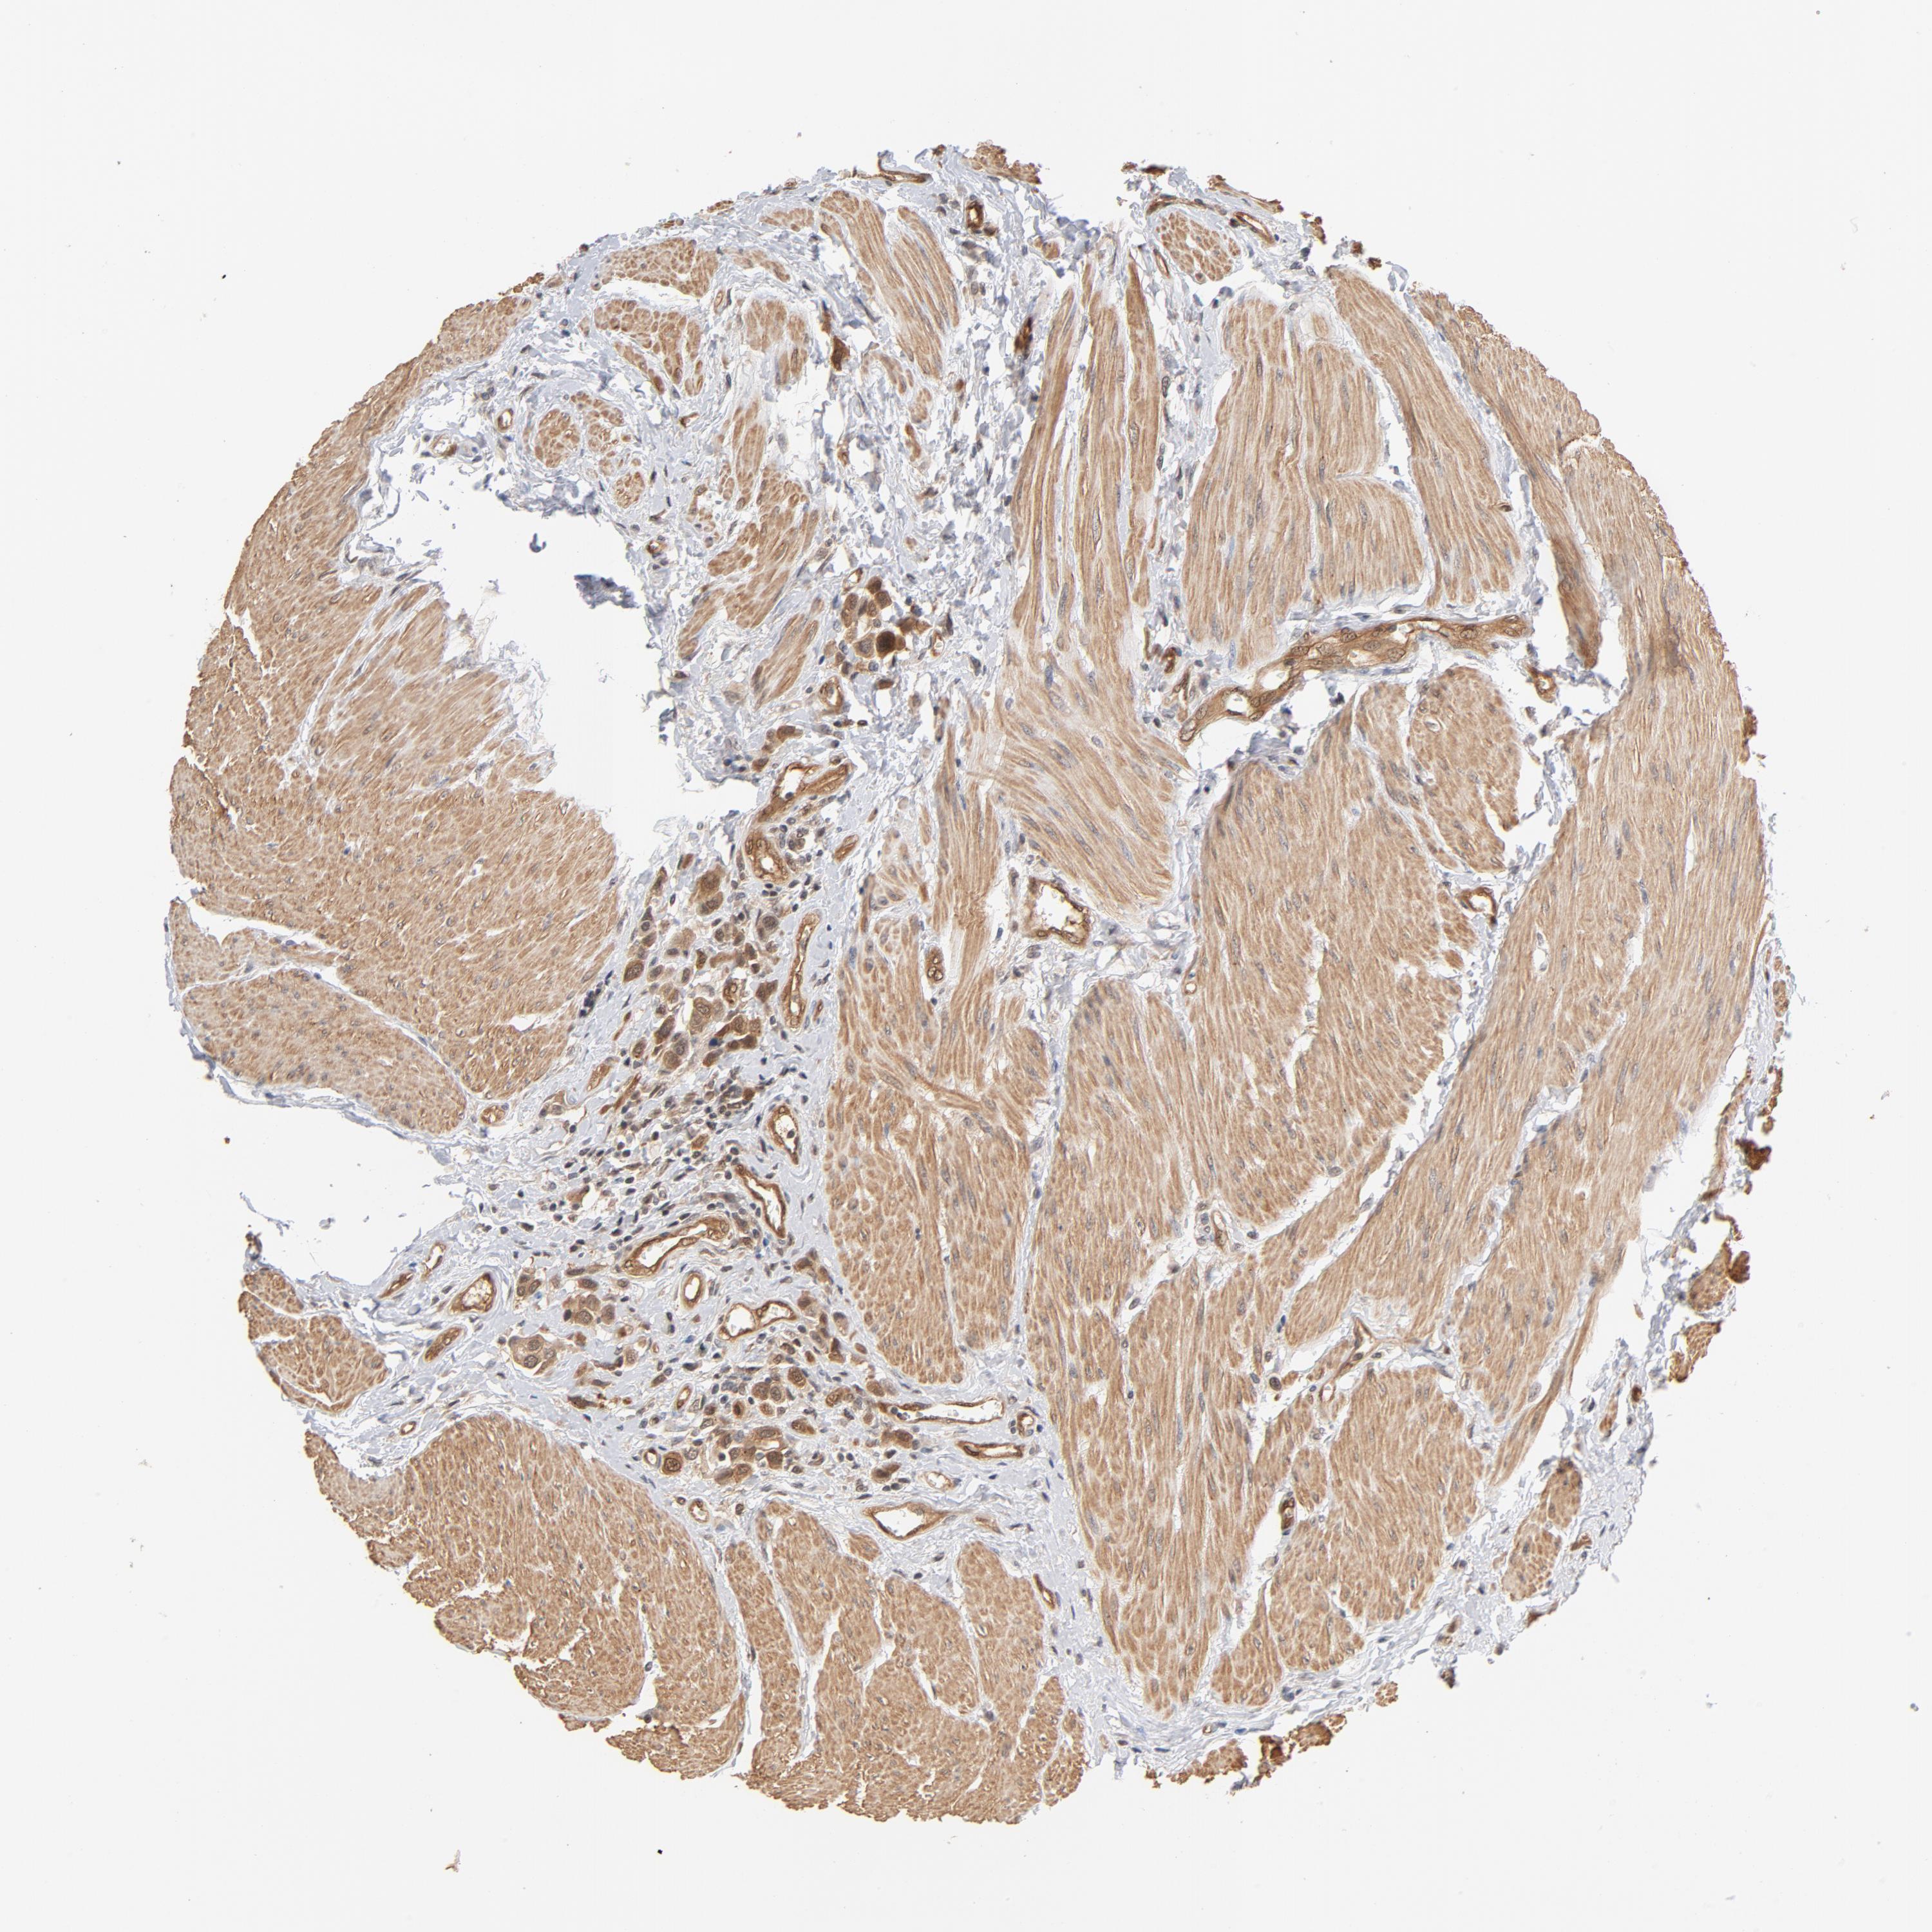

UROTHELIAL CANCER - Protein expressioni

A mouse-over function shows sample information and annotation data. Click on an image to view it in a full screen mode. Samples can be filtered based on level of antibody staining by selecting one or several of the following categories: high, medium, low and not detected. The assay and annotation is described here.

Note that samples used for immunohistochemistry by the Human Protein Atlas do not correspond to samples in the TCGA dataset.

Antibody stainingi

Antibody staining in the annotated cell types in the current human tissue is reported as not detected, low, medium, or high, based on conventional immunohistochemistry profiling in selected tissues. This score is based on the combination of the staining intensity and fraction of stained cells.

Each image is clickable and will lead to virtual microscopy that enables deeper exploration of all samples and also displays staining intensity scores, fraction scores and subcellular localization as well as patient and tissue information for each sample.

Antibody HPA003928

Antibody CAB004214

Urothelial carcinoma, High grade

Urothelial carcinoma, Low grade